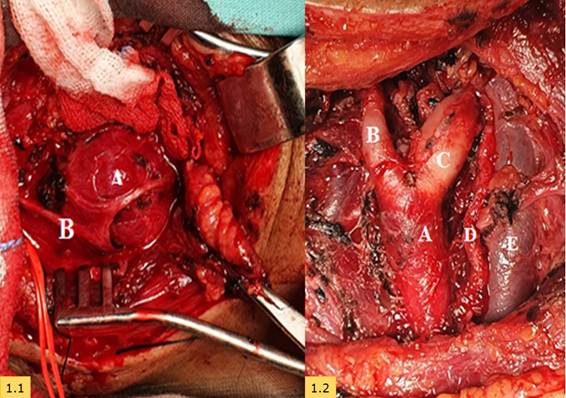

Figura 1.1/1.2 Abordaje cervical izquierdo. Esternocleidomastoideo debatido en plano profundo. Se observa A) Glomus carotideo cubierto por el B) nervio hipogloso./Disección completa de tumor, A) Arteria carótida común y bifurcación carótida y ramas B) interna y C) externa. D) Nervio hipogloso, E) Vena yugular interna.

Se procedió a la asepsia, antisepsia, preparación de campo operatorio. Se ingresa con disección por delante del músculo esternocleidomatoideo. Se advierten los siguientes hallazgos intraoperatorios: visualización contralateral de la arteria carótida común central de la masa tumoral entre las carótidas. Se inyecta lidocaína en adventicia. Resección y reparación del tumor de las paredes arteriales. Se evidencia que las paredes arteriales son delgadas. Se quita el tumor de 4x3cm, los diámetros de las ramas son muy pequeñas, se realiza a hemostasia. Se procede al cierre de los planos, se coloca drenaje en región de la incisión con gasas y se da por terminada la cirugía, el cuál fue un procedimiento sin complicaciones.